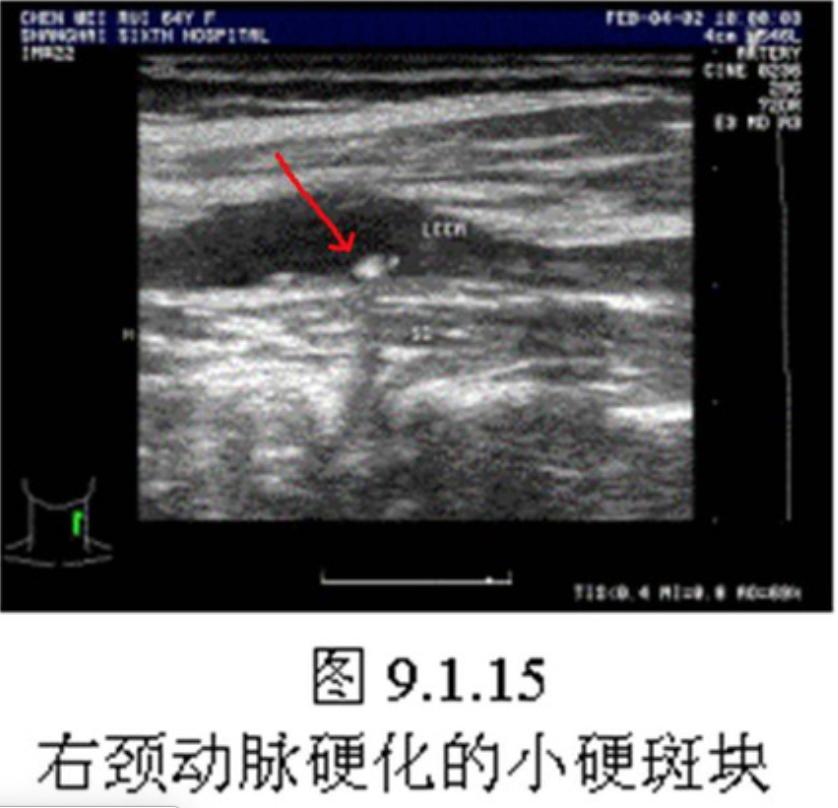

第一,颈部的斑块是低回声的(也就是软斑块);